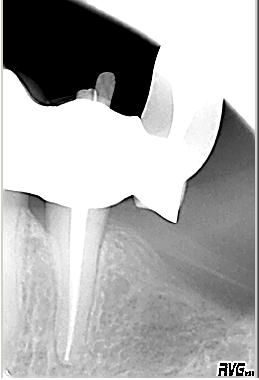

Röntgenologischer Ausgangsbefund im Januar 1993 bei Zahn 34 unmittelbar vor ZE Neuversorgung. Als sicheres Zeichen für das Vorhandensein zweier Kanalsysteme ist das scheinbar abrupte Verschwinden des im koronalen Wurzeldrittels deutlich sichtbaren „Pulpastumpfes“ zu werten

Distalexzentische Aufnahme

Distalexzentische Aufnahme mit zweitem Parodontalspalt im November 2002 wegen Schmerzen